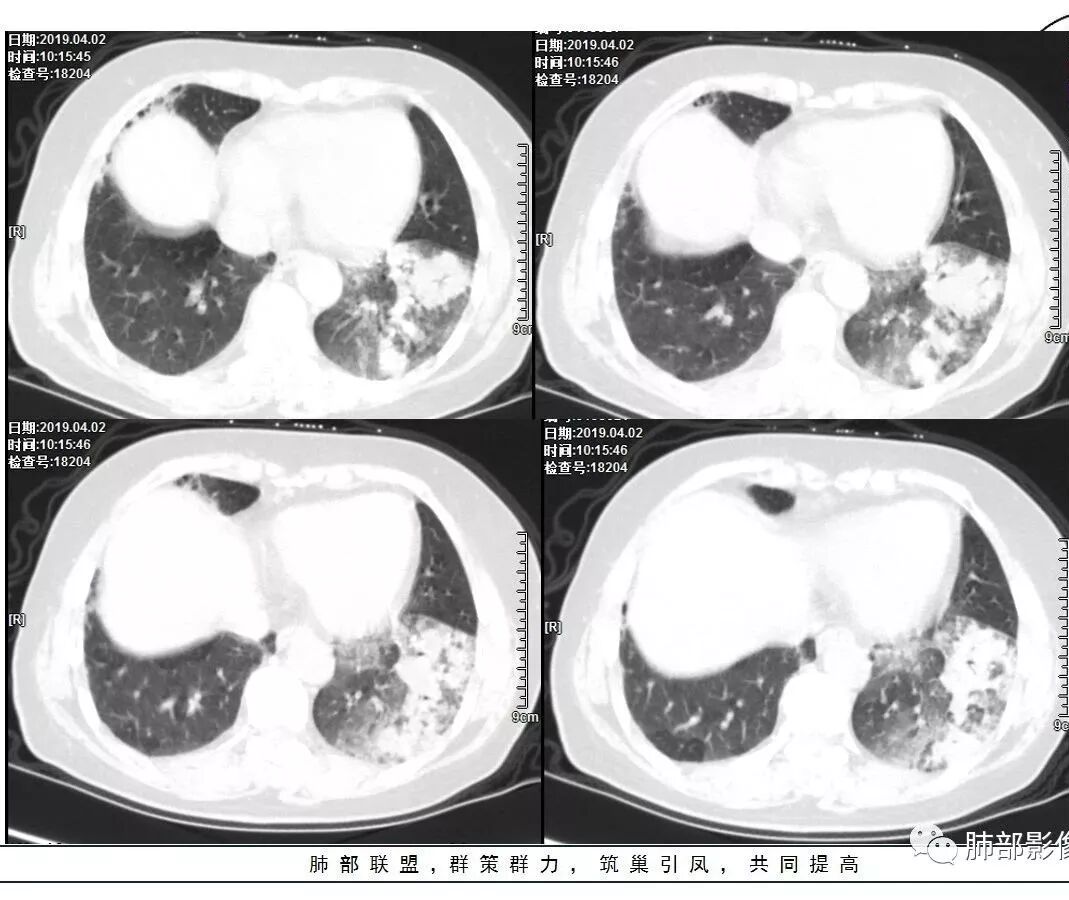

女性,57岁或67岁,咳嗽气短2月,伴发热2天。肿标及血常规(一)。左下肺实变+GGO,实变区增强强化,镜下见左下支气管狭窄,最后一次CT(4.11)较第一次CT(3.24)病灶有吸收。个别图像看不清(Tspot)。考虑:一元:肺炎型肺癌丶肺结核丶普通炎症?二元:结核合并癌?

2.左肺下叶片状影及多数有边界的结节影,较散,多形性,密度不均(注意许多老师提到这个特点还是比较明显的)。左肺下叶体积未见缩小。

3.病灶强化比较明显。

1.前述特点除强化外都还是很容易让人首先想到肺结核的可能性。结核是常见病。注意肉芽肿明显的结核灶可以观察到强化。

2.淀粉样变性病变支气管改变一般会更广泛,较少出现单叶肺的如此大片影。

3.腺癌不大会出现较散的腺泡样结节影,更不会出现如本例的支气管改变。增大钙化的淋巴结也很难相互关联。